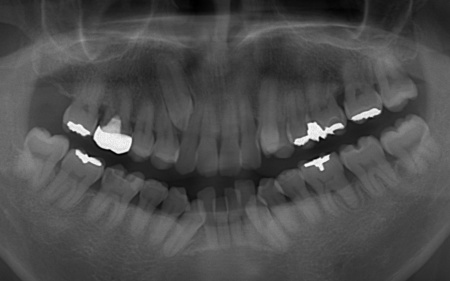

| カウンセリング | 拝見したところ、上下の歯は、ずれたりねじれたりしてデコボコに生えており、著しく歯並びが乱れていました。

またレントゲン撮影をして確認すると、右上前歯は顎の骨の中に埋まっている骨性埋伏(こっせいまいふく)の状態でした。 さらに、左下奥歯は重度の歯周病であり、歯を支えている骨が一部溶けていることが判明しました。 以上のことから、歯並びを整える矯正治療と歯周病の治療を併せて行う必要があると診断しました。 |